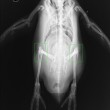

ROMA – Anche i pinguini hanno le ginocchia. Questi adorabili animali, hanno le stesse ossa delle gambe presenti nella maggior parte dei vertebrati bipedi. A differenza però degli altri vertebrati, parte di queste ossa sono coperte dalle piume.